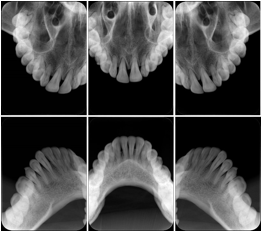

2 Occlusal Vertical Maxilla A Dental Image Layout

DL-C001A

Reference: DL-C001-U1L0

Reference: DL-C001-U2L0

2 Occlusal Vertical Mandible A Dental Image Layout

DL-C002A

Reference: DL-C002-U0L1

Reference: DL-C002A-U0L2

2 Occlusal Horizontal Maxilla A Dental Image Layout

DL-C003A

Reference: DL-C003-U1L0

Reference: DL-C003-U2L0

2 Occlusal Horizontal Mandible A Dental Image Layout

DL-C004A

Reference: DL-C004-U0L1

Reference: DL-C004-U0L2

3 Occlusal Vertical Maxilla A Dental Image Layout

DL-C005A

6 Occlusal Vertical A Dental Image Layout

DL-C007A